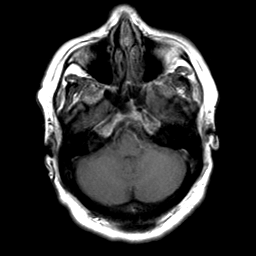

Cerebral hemorrhage, MR Study mr-t1 -- Slice #6

[Home][Help][Clinical] Slice 6